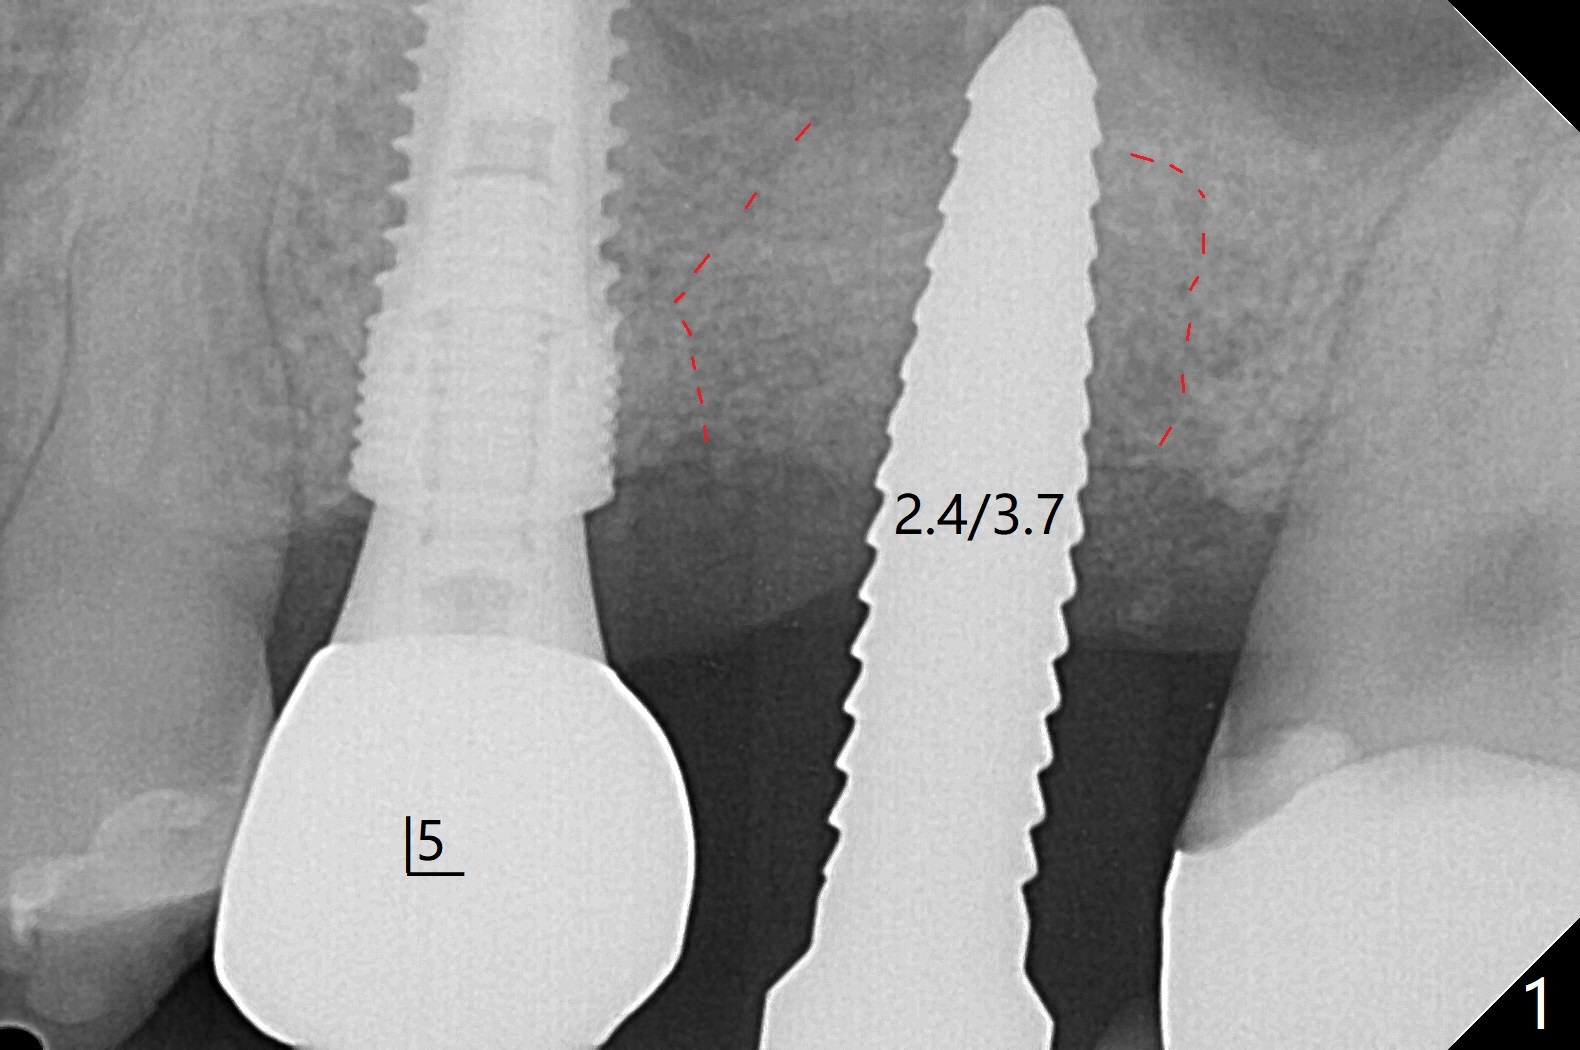

60岁男,左上6(牙根折裂严重骨质吸收)位点保存后6个月,回来植牙。术前CT显示骨质密度低,宽度足够,角化龈也宽,前后牙齿都有牙冠,制作导板麻烦,所以采纳徒手种植。使用4毫米活检打孔刀(Biopsy Punch)进入,简化手术,但是又怕开口不正,不敢用大号植体,术后CT发现钻洞偏颊侧。针对骨质密度低,使用1.2毫米钻头后(约8毫米),使用旋转式骨扩张器直至2.4/3.7毫米(图一(红虚线:原来骨质缺损)逐渐增加深度至11毫米),备洞几乎没有失去骨质,钻洞周围骨质密度谅必增高),取出最后一个扩大器后发现上颌窦底板破裂,放置粘性骨粉,使用4毫米报废植体做上颌窦提升,重复一次(图二,三),稳定性尚可。再次放置骨粉和PRF膜,使用正式植体提升(4.5x8毫米),临床上很难判断是否植体植入牙槽嵴之下(可能骨质疏松),只好拍摄CT(图四,五),好像正好牙槽嵴下,不过又植入骨粉一些(图七:*)。植体扭力~15Ncm,保险起见,放置愈合帽,表面放置少许骨粉以及打孔留下的牙龈(图六:G,之前一直泡在PRF上清液里),牙周胶水固定游离牙龈以及牙周敷料保护。术后6小时没有鼻出血。所以骨质缺损严重,植骨后,虽然缺损外形得到恢复,但是骨头质量,固定植体能力还不够。植牙时,需要适当改变手段,例如使用骨凿,提高骨质密度,而不是单纯使用钻头。术后病人恢复正常,没有疼痛,六天复诊,牙周敷料已经脱落,打孔的牙龈附着颊侧,部分骨粉暴露,但是看样子挺稳定,好像游离牙龈必须缝合。使用树脂敷料牢靠些。术后五周,伤口基本愈合,一处未愈合,与下面骨粉相通,用牙周探针稍微搅动,出血(图九)。擦干血迹,伤口还不错(图十)。术后2个月伤口好像正常愈合(图十一)。术后4.5个月根尖片显示6种植比5深,往后螺纹暴露可能性减少(图十二)。